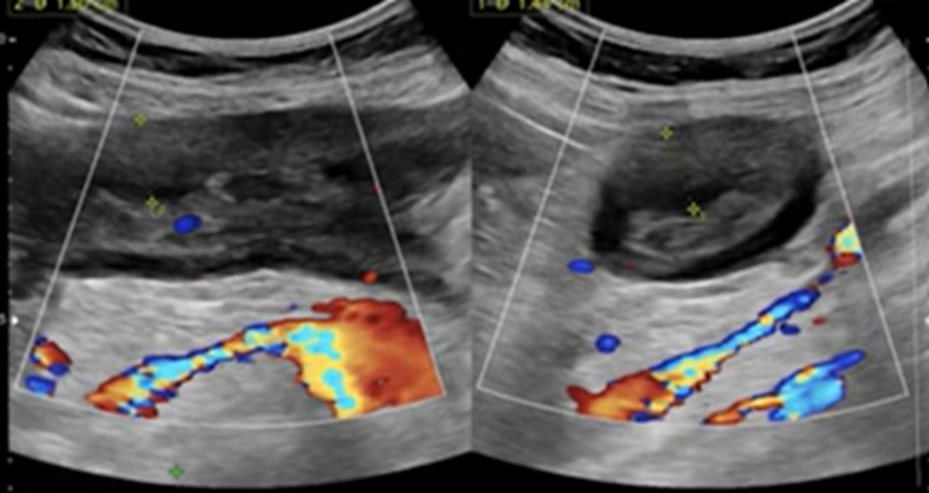

En Flanco izq en región de dolor, en relación a colon descendente, marcado engrosamiento de aspecto nodular, hipoecogénico y heterogéneo con moderada hiperemia al Doppler color y power. En signo de pseudoriñon, con leve aumento de la ecogenicidad de la grasa adyacente. Hallazgos sugerentes de adenocarcinoma

Se explora dirigidamente flanco izquierdo, donde en correspondencia con área de sensibilidad al paso del transductor, se identifica engrosamiento focal de la pared del colon descendente, con aumento de la vascularización al Doppler Color. Se esboza imagen de pseudoriñon, con aumento de la ecogenicidad de la grasa circundante.

Impresión: Hallazgos ecográficos compatibles con engrosamiento focal de la pared del colon descendente, con imagen de pseudoriñon. De acuerdo a criterio clínico se sugiere tomografía computada contrastada para descartar proceso proliferativo, así como sospecha de intususcepción en evolución.